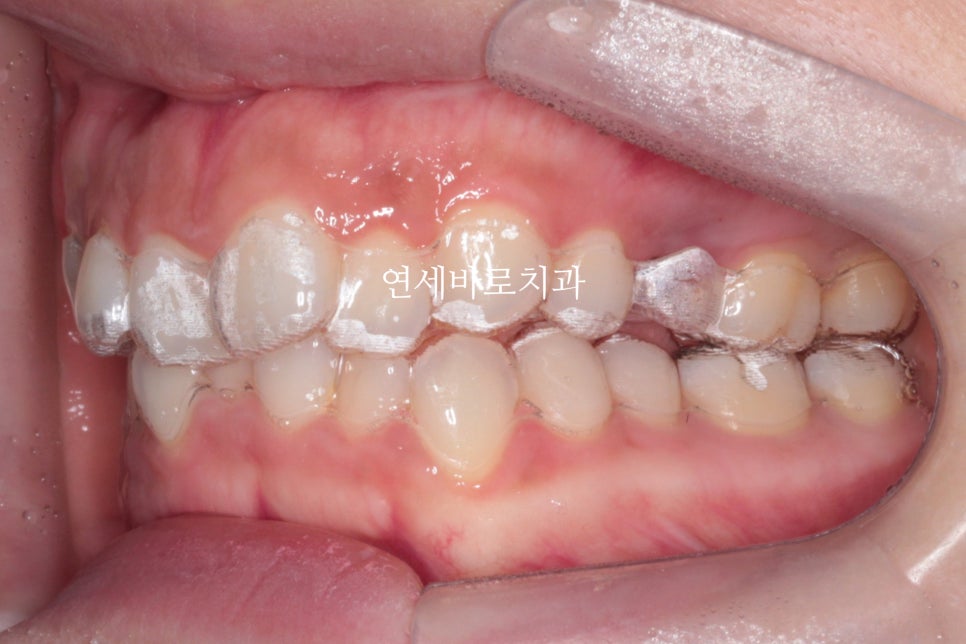

이 사진은 첫날 인비절라인을 착용하였을때의 사진입니다.